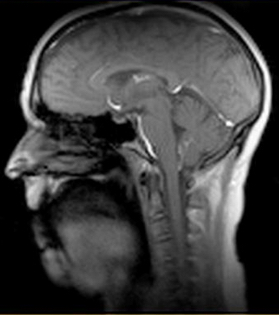

High-speed MRI technique captures complex vocal movements at 100 frames per second

Demonstrated with Wizard of Oz song “If I Only Had a Brain”